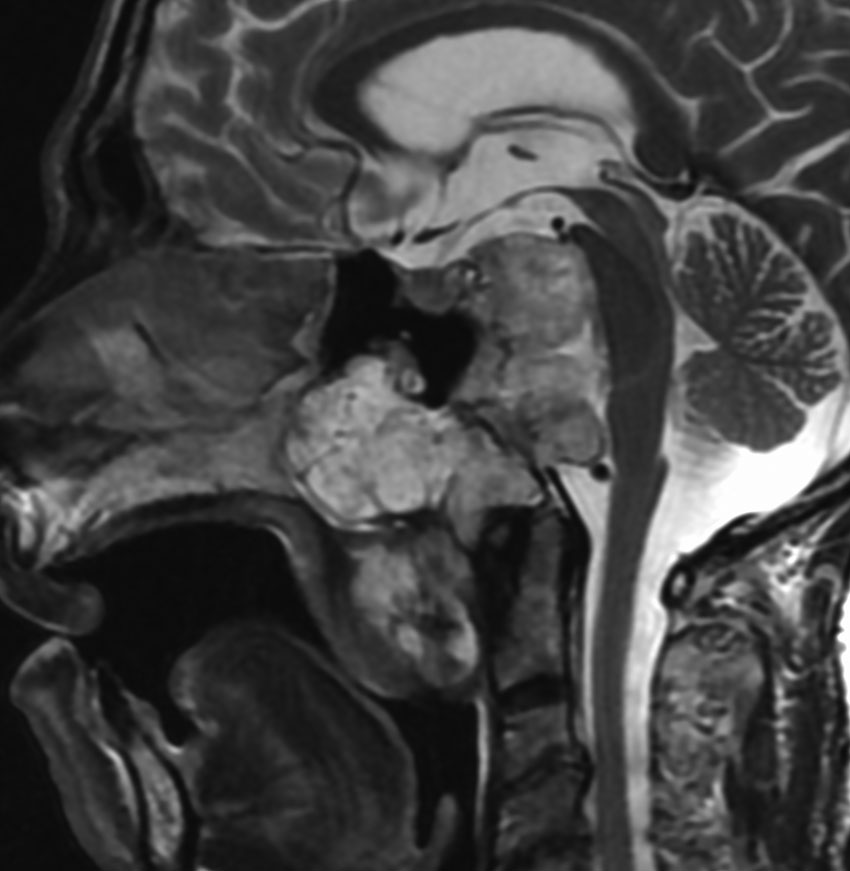

治療しないで経過を見ること

10年間さしたる症状もなく,経過観察されてきた巨大な脊索腫です。右三叉神経障害,外転神経麻痺,聴力消失などの症状が順次にでました。やがて上咽頭に腫瘍が進展して気道狭窄になりました。もともと全摘出できないものなので,主治医の先生の経過観察をできるところまでするという方針も納得ができるものです。

CTでは,斜台から左蝶形骨にかけて不規則な骨破壊像がみられます。

MRI T2強調画像(左)では等信号から高信号のまだらな境界が不明瞭な腫瘍が斜台から左海綿静脈洞内に浸潤しているのがみられます。T1強調ガドリニウム増強では,腫瘍がまだらに増強されています。トルコ鞍から鞍上部に伸び,視交差を侵し第3脳室底まで伸展しています。脊索腫が硬膜内に浸潤して神経組織と癒着することは珍しいことではありません。